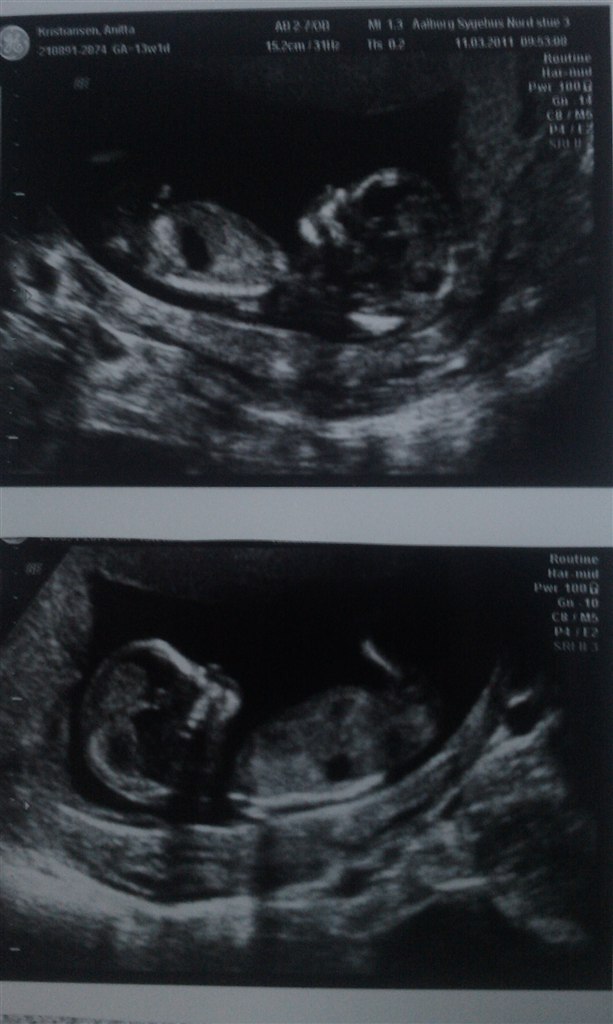

var helt solgt da jeg så den ligge og sparke og slå ud med armene.

Ej, sikke nogle skønne billeder

Synes det er helt vildt så meget de ligner små mennesker i en størrelse af 6-7 cm... Det er bare for vildt